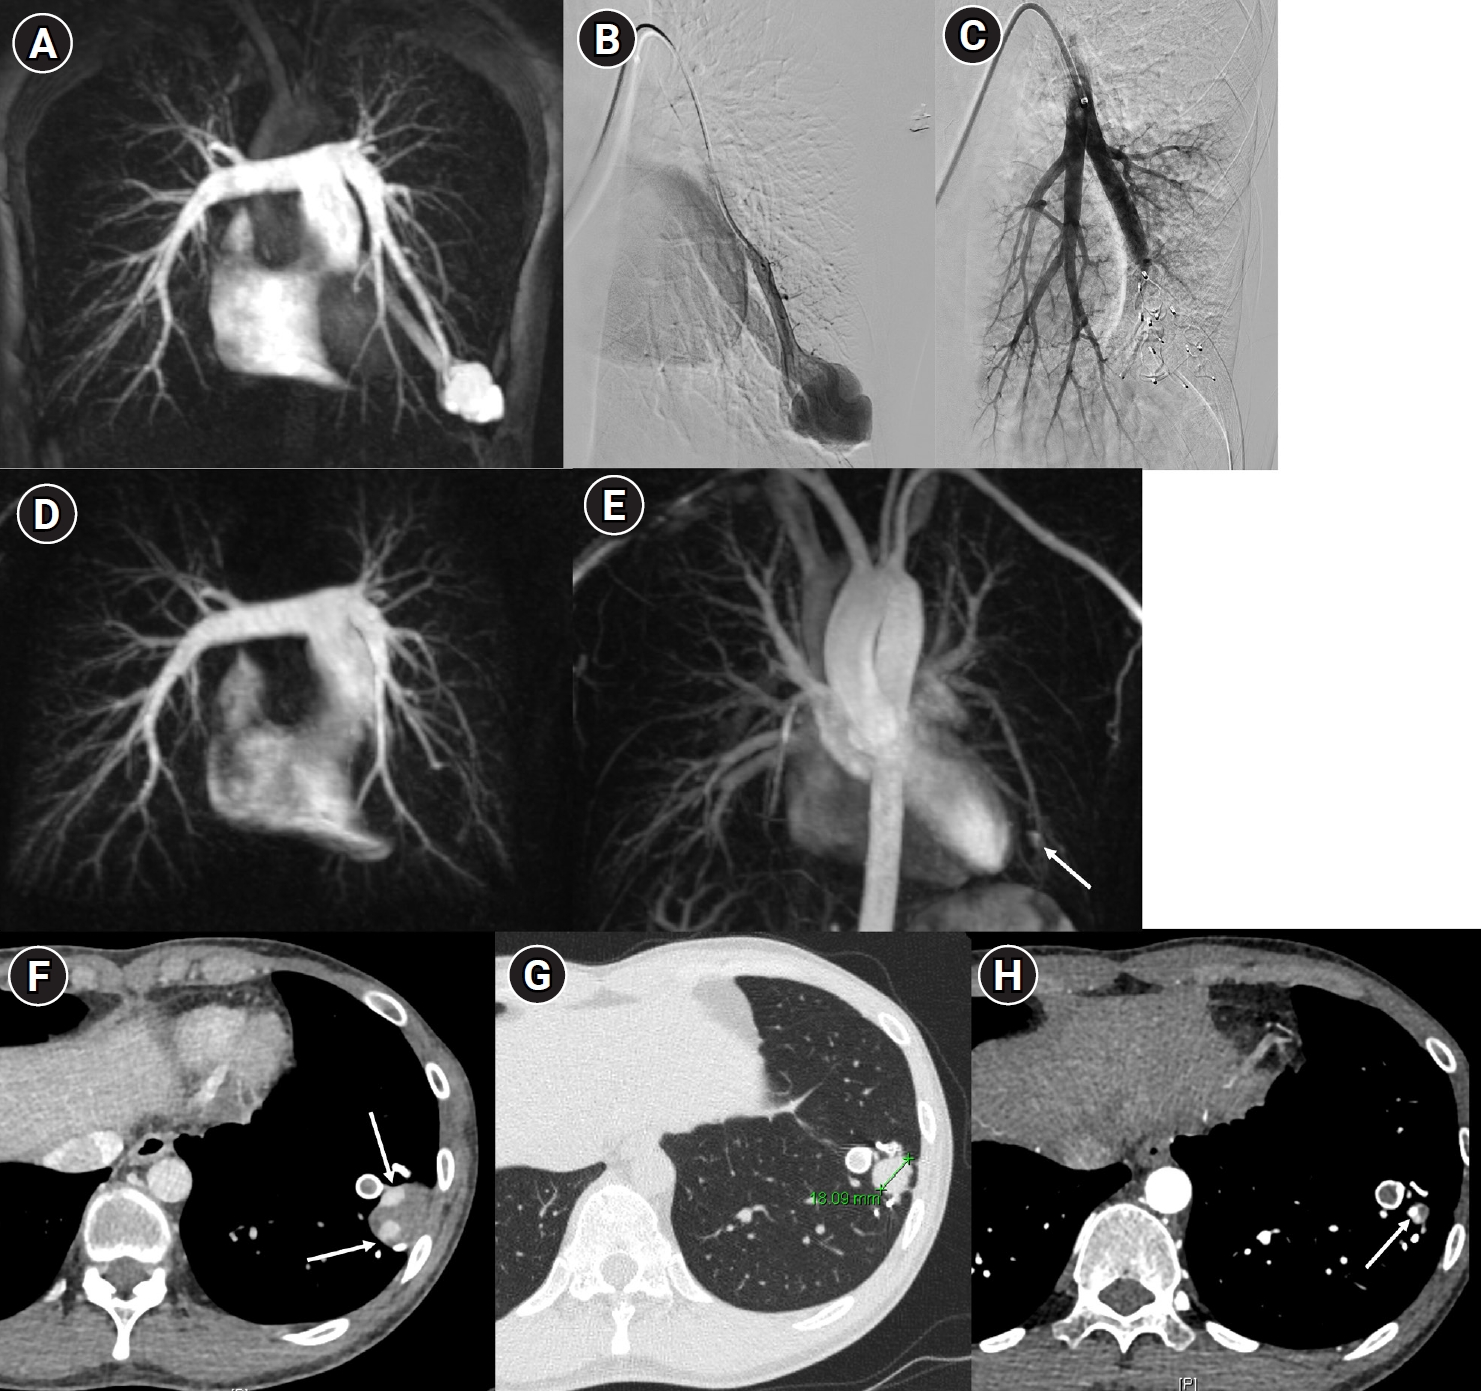

Fig. 10.

Images before and after embolization using a vascular plugs in a patient with a large pulmonary arteriovenous malformation (PAVM) in the left lower lobe. (A) In the time-resolved MR angiography, a PAVM in the left lower lobe exhibiting an early draining vein is observed. (B, C) The pulmonary arteriography also shows the same findings, and feeding artery embolization was performed using one Amplatzer vascular plug type II and six Amplatzer vascular plugs type IV devices. (D, E) In the 6-month follow-up time-resolved MR angiography, no rapidly appearing vein is observed in the arterial phase, and in the delayed phase, there is enhancement within the venous sac (arrow), which is considered part of the normal draining vein. (F–H) In the computed tomographic images taken at 1 month (F), 6 months (G), and 18 months (H) post-treatment, the thrombosed venous sac gradually diminishes, leaving only the normal draining vein (arrows) inside.

Fig. 10. Images before and after embolization using a vascular plugs in a patient with a large pulmonary arteriovenous malformation (PAVM) in the left lower lobe. (A) In the time-resolved MR angiography, a PAVM in the left lower lobe exhibiting an early draining vein is observed. (B, C) The pulmonary arteriography also shows the same findings, and feeding artery embolization was performed using one Amplatzer vascular plug type II and six Amplatzer vascular plugs type IV devices. (D, E) In the 6-month follow-up time-resolved MR angiography, no rapidly appearing vein is observed in the arterial phase, and in the delayed phase, there is enhancement within the venous sac (arrow), which is considered part of the normal draining vein. (F–H) In the computed tomographic images taken at 1 month (F), 6 months (G), and 18 months (H) post-treatment, the thrombosed venous sac gradually diminishes, leaving only the normal draining vein (arrows) inside.